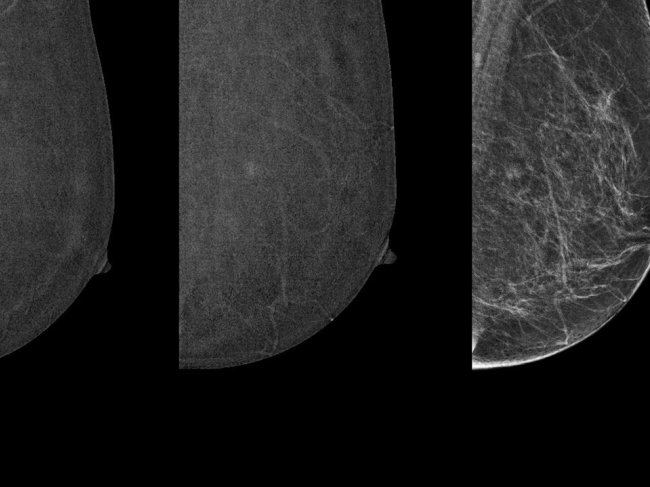

Uma solução inovadora que utiliza inteligência artificial (IA) para auxiliar os nossos radiologistas na deteção precoce do cancro da mama.